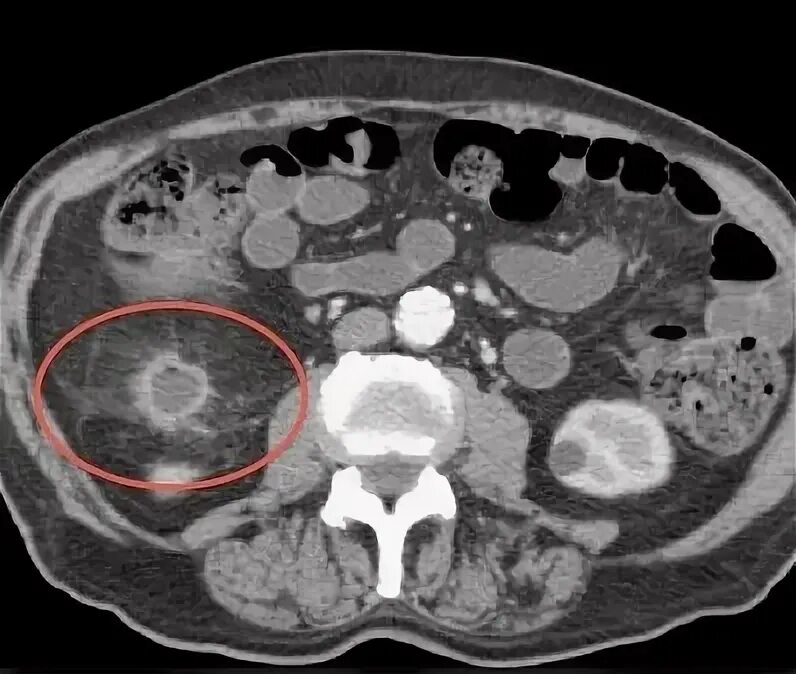

Как выглядит кт с контрастом